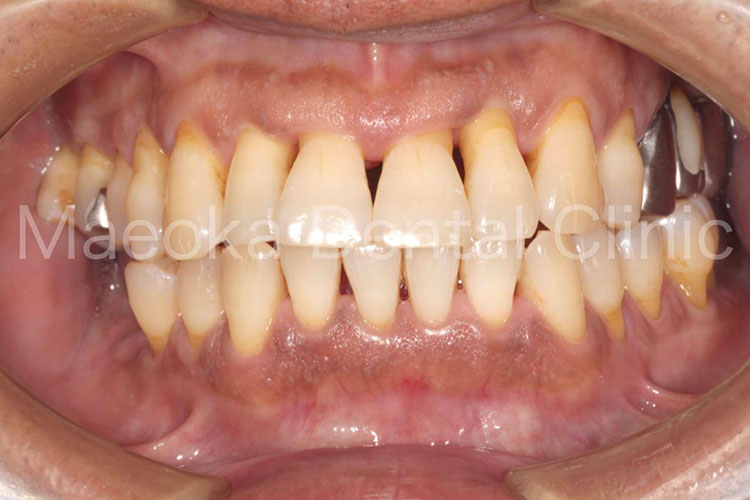

患者さんは58歳の男性の方で、「右下の歯がグラグラして痛いので診て欲しい」という主訴で来院されました。お口の中を拝見すると重度の歯周病を認めました。1日1箱近い本数の喫煙があったこともあり、歯肉は血行不良を起こして黒っぽい印象がありました。

初診時には歯周病の原因と「どうすれば歯周病は治るのか」、「再発を防ぐためには何が必要なのか」を説明し、歯磨きのトレーニングをスタートしました。その後、患者さんのプラークコントロールレベルが向上したタイミングで歯石を取り、基本治療を終えました。その後、義歯を入れるなどの機能回復も検討しましたが、患者さん自身が不都合を感じていなかった点、レントゲン上でも残存歯の負担が増加している所見が見られなかった点を考慮し、経過観察としています。

主訴の右下7は失うことになってしまいましたが、その他の歯は現在のところ1本も失うことなく経過しています。現在も喫煙はありますが、歯肉は引き締まり、健康な組織を取り戻しています。今後はメインテナンスを通してプラークコントロールレベルの維持に患者さんと取り組んでいきます。

治療後(左側方面)